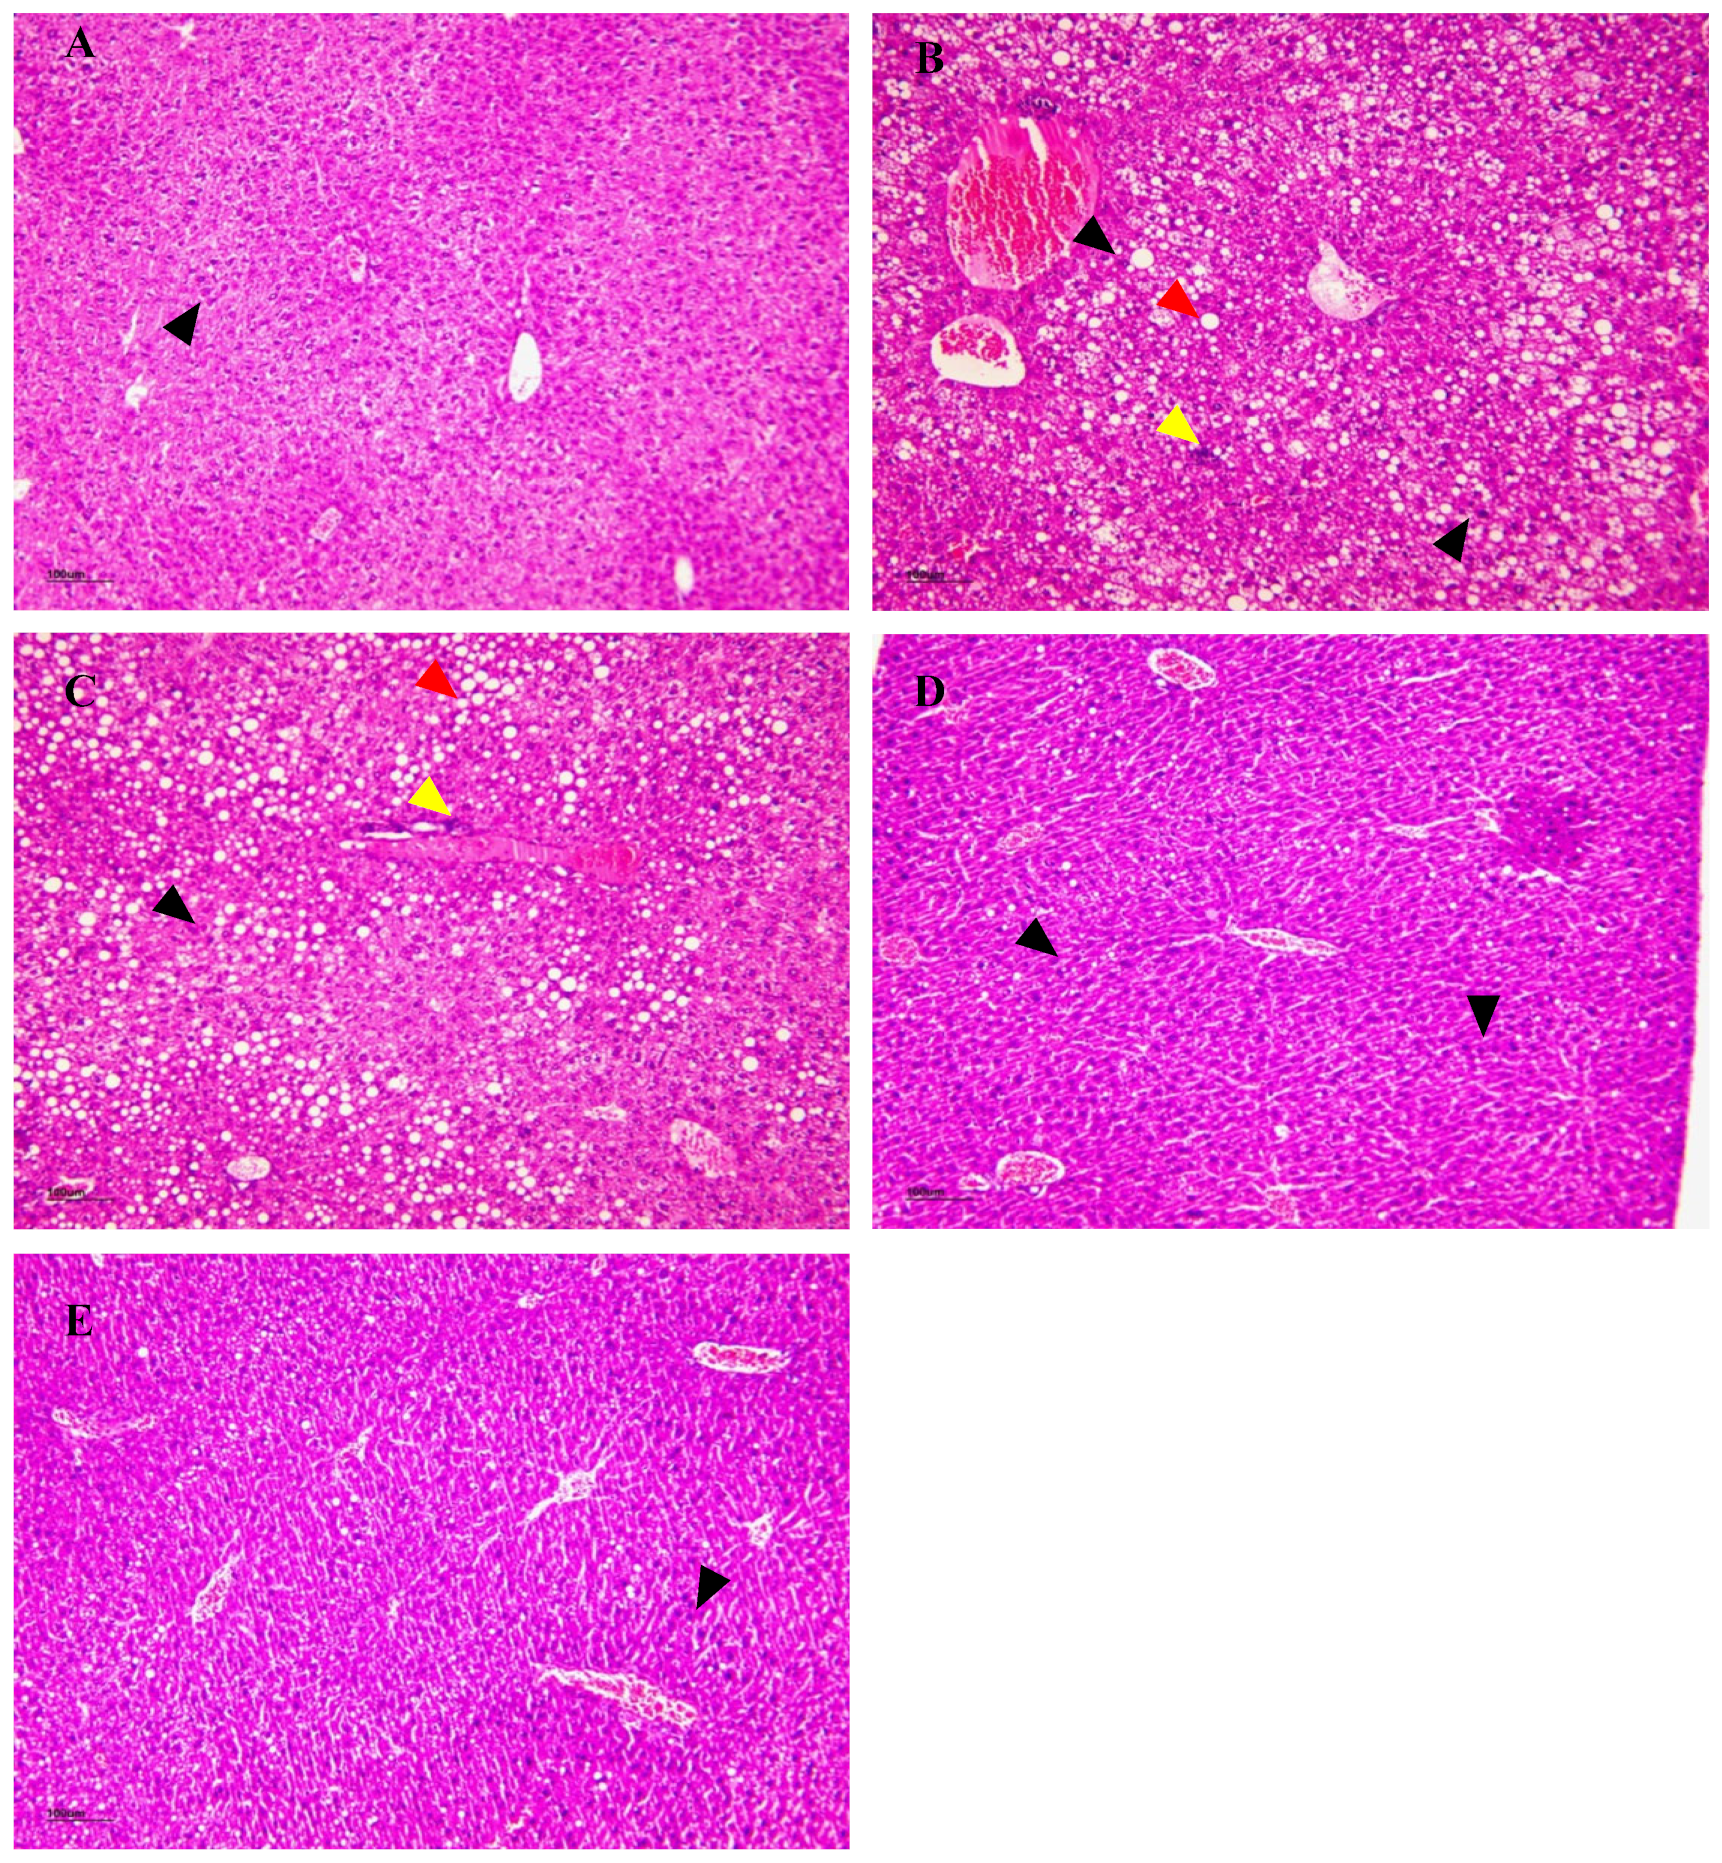

3.15. The Effect of NSPs on Liver Histology

3.15.1. H&E Staining

3.15.2. Oil Red O Staining